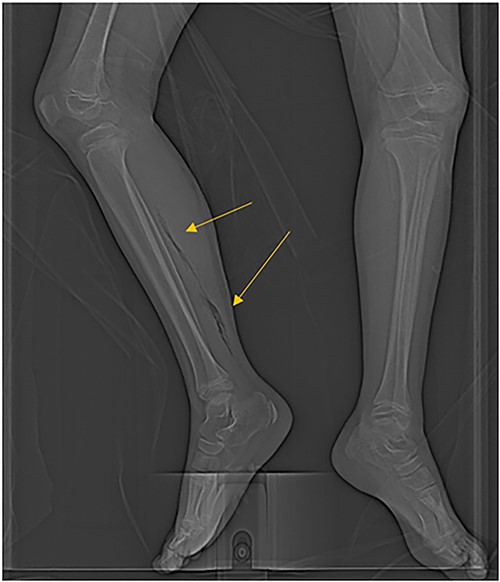

The patient was an 8-year-old female who presented to hospital with a 3-day history of fever, abdominal pain, and coffee ground emesis. On presentation, she was afebrile, tachycardic, and hypotensive. On examination, she had an acute abdomen and septic shock. Initial laboratory investigations revealed a venous pH of 7.08, CO2 of 47 mmHg, bicarbonate of 14 mmol/L, lactate of 3.9 mmol/L, white blood cell count of 3.7 × 109/L with an absolute neutrophil count of 0.96 × 109/L, C-reactive protein of 389 g/L, INR of 1.7, PTT 36 s, fibrinogen of 5 g/L, and an acute kidney injury with a creatinine of 100 micromoles/L and urea of 10 mmol/L. An abdominal ultrasound revealed a starry sky appearance of the liver with moderate free fluid in the right upper quadrant. She was not fluid-responsive and thus was treated with an epinephrine infusion and empiric antimicrobial therapy with ceftriaxone and vancomycin. Transportation was arranged to a tertiary care center with access to pediatric intensive care and surgical services. In transport she developed mild erythema to the right calf with severe pain to palpation and dorsiflexion out of proportion of clinical findings (Fig. 1). Her creatine kinase level was 10 000 U/l and a computerized tomography (CT) scan of the right leg demonstrated extensive soft tissue gas and myonecrosis (Fig. 2). An abdominal CT scan demonstrated evidence of bowel perforation in the right lower quadrant with associated loculation, intra-abdominal free air and fluid, and proximal bowel dilation (Fig. 3). Considering these findings, antibiotics were broadened to piperacillin-tazobactam, vancomycin, and clindamycin, and she was urgently taken to the operating room.

The patient’s right leg upon presentation to the tertiary care hospital, with the area of erythema and edema outlined with a skin marker.

CT scan demonstrating extensive air in the soft tissue of the right leg.